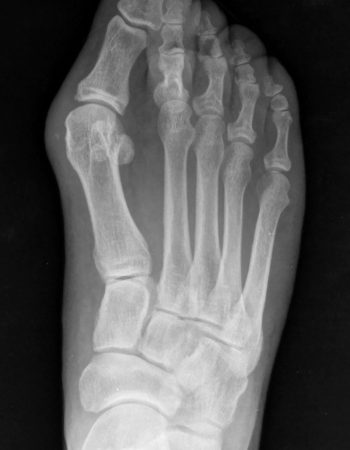

El caso que presentamos es muy representativo de la capacidad de corrección de la cirugía percutánea de tercera generación en la deformidad de Hallux Valgus. Se trata de una paciente con dolor a nivel del bunion y metatarsalgia con un 2º dedo sobre el primero que también le causa intolerancia con el calzado. Fue sometido a una técnica percutánea llamada MICA (Minimal Invasive Chevron Akin), sin ingreso y permitiendo carga inmediata

En las imágenes radiográficas se observa cómo se consigue una gran corrección en la posición de los dedos y una reducción de los sesamoideos sobre la cabeza metatarsiana. La fijación con tornillos nos va a permitir mantener esa reducción y estabilizar el montaje para reducir el dolor postoperatorio y permitir una buena consolidación ósea, como se ve en la última imagen.